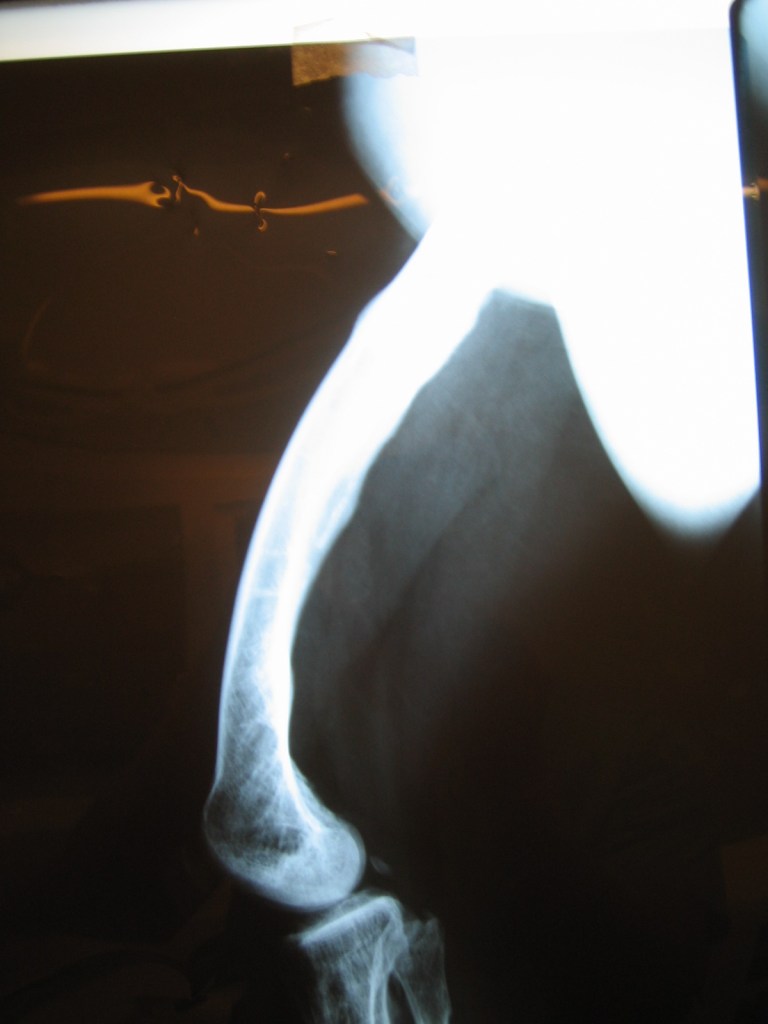

Leonardo Saldaña

Mensaje de Agradecimiento

tras múltiples cirugías y una osteomielitis grave en mi pierna , la única opción que me daban era la amputación con desarticulación , fue mi hermana quien consulto en Cotram con el Dr Dratewka quien me propuso un tratamiento para tratar la infección y al mismo tiempo reconstruir mi hueso faltante

Tras dos años puedo decir que valió la pena el esfuerzo